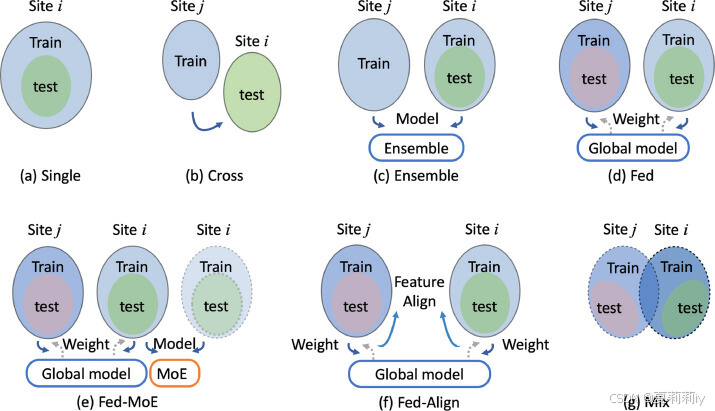

③Domain adaptation strategies with FL:

2.5.3. Comparisons with different strategies

①Evaluation methods:

②Comparison result: